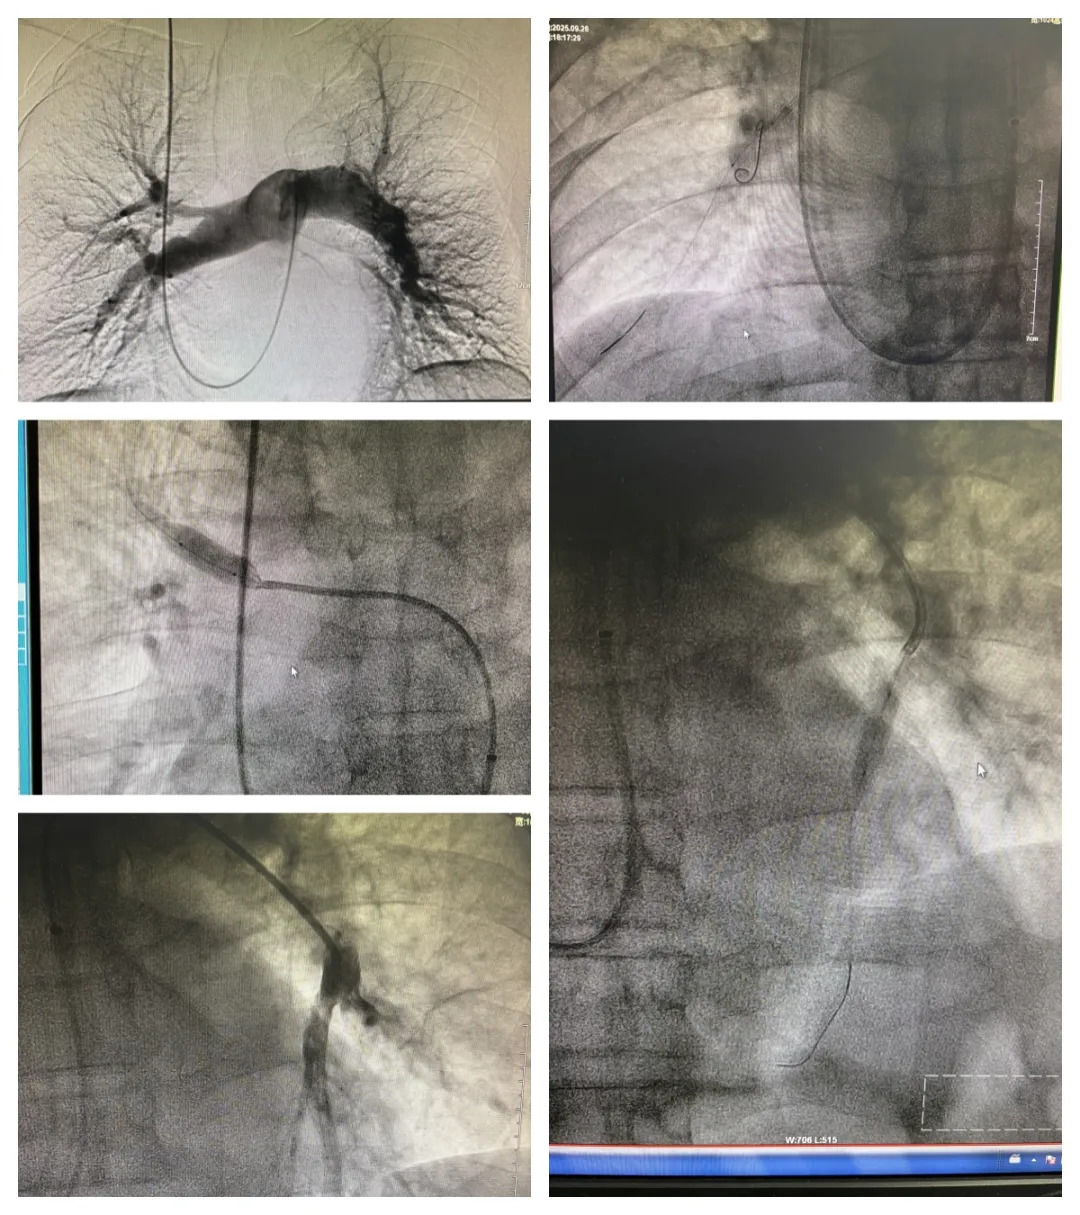

心血管内一科医护团队一致认为患者需行右心导管测压、肺动脉造影、肺动脉球囊扩张术。与患者及家属详细沟通后,同意手术治疗。术前准备就绪后,在西安交通大学第一附属医院张松林教授指导下,心血管内一科主任翟向伟、副主任医师陈万林及介入导管室团队密切配合,顺利完成手术。因患者之前植入的下腔静脉滤器未取,手术团队穿刺右侧颈内静脉经导管测平均肺动脉压力50mmHg(重度),进一步行肺动脉造影提示患者双侧肺动脉多发严重狭窄,部分肺动脉闭塞。介入团队随后依次对左右肺动脉狭窄病变进行球囊扩张成形术(共扩张肺动脉5支),术后患者胸闷气短症状明显减轻。经过医护团队的精细治疗及护理,患者顺利出院。择期将再次行肺动脉球囊扩张术。